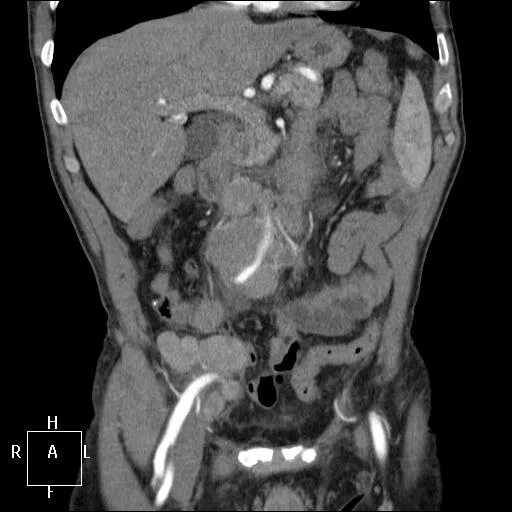

Кт брюшной полости краснодар